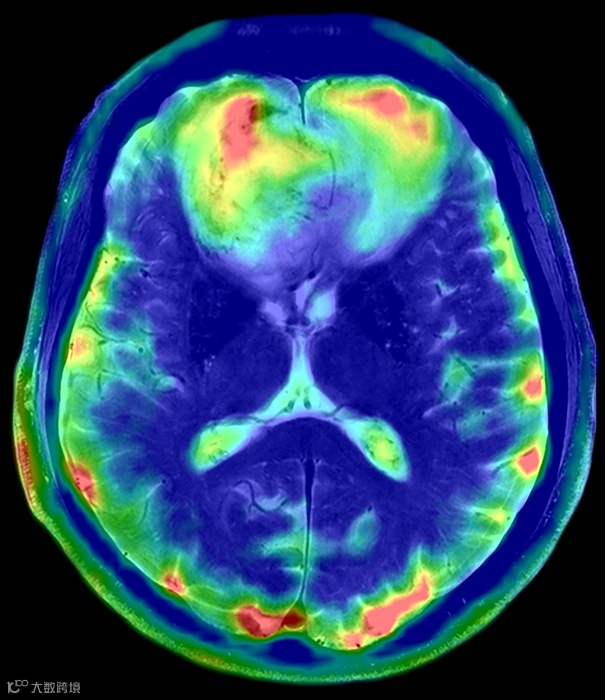

多核磁共振突出的是MRI,也就是磁共振成像。比如,我们传统的磁共振得到的图像,反映的是氢质子的信息,你可以理解为氢图。而多核磁共振,我们就可以得到比如钠图,磷图,氟图....。

如图10所示,为不同场强下多核钠成像图。可以发现常规场强的1.5T或3.0T进行多核成像是比较吃力的,得到的图像由于信噪比太低,灵敏度明显不够。